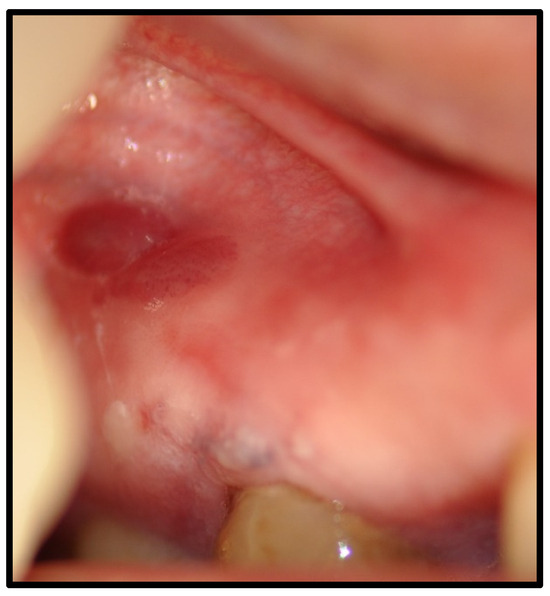

| OLP/lichenoid reaction (3 were exacerbations of previous autoimmune disease) | 12 | 50.00 | |

| Benign mucous membrane pemphigoid | 3 | 12.50 | |

| Management | Costicosteroid mouthwash, with good response | ||